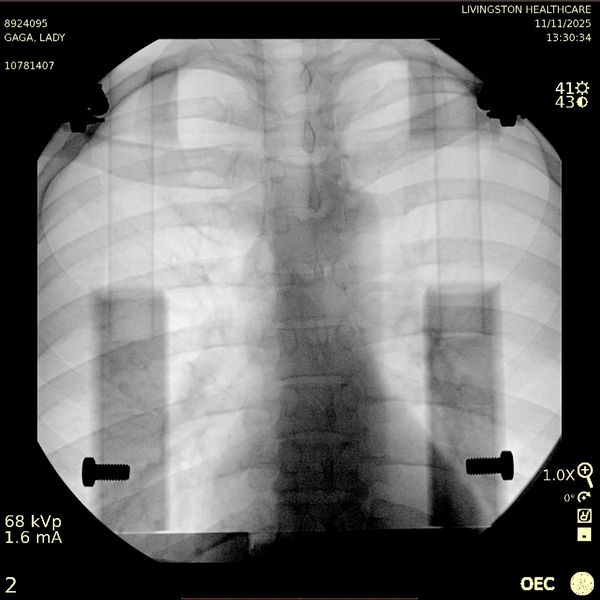

Radiolucent Patient Positioning Device

Design and manufacture a radiolucent patient-positioning device that enables modular attachment to multiple table systems, can be securely fixed in variable positions, and maintains a low-profile form factor while allowing unobstructed imaging along the spinal column.